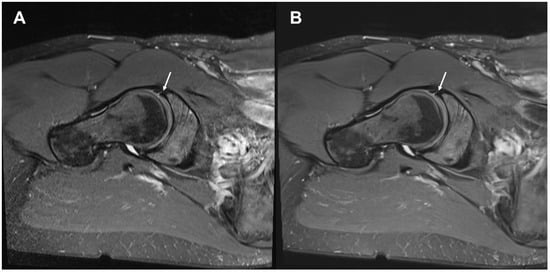

3.2. Delineation of Anatomic Structures and Internal Derangement